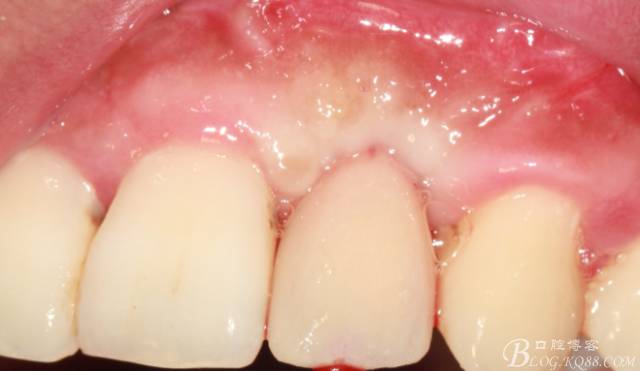

10天拆線一切正常,又過(guò)了兩周患者復(fù)診,自述期間無(wú)異常??趦?nèi)檢查,真的嚇了一跳,唇側(cè)鼓了個(gè)包,擠壓有白色分泌物溢出,絕對(duì)不是膿液,液體排除后,術(shù)區(qū)觸診空虛,外觀塌陷。這時(shí)候考研大夫的時(shí)刻到了,是先觀察一段時(shí)間再說(shuō)?還是馬上進(jìn)行處理?我的回答是:馬上處理!如果你沒(méi)有及時(shí)處理,而是放患者回家觀察,那么接下來(lái)會(huì)發(fā)生如下情況:1.回家后患者家屬及親友會(huì)有很多你可以想象得到的討論;2.患者及家屬會(huì)對(duì)你產(chǎn)生不信任,勢(shì)必會(huì)到其他門診或醫(yī)院檢查,他院大夫會(huì)不會(huì)發(fā)表對(duì)你不利的言論;3甚至?xí)蚁嚓P(guān)法律界人士找你討要說(shuō)法。

于是我果斷告知患者,手術(shù)失敗了,不能拖延,如不及時(shí)處理,炎癥繼續(xù)發(fā)展會(huì)很快波及鄰牙牙槽骨?;颊呓邮芪业慕ㄗh。切開(kāi)翻瓣,骨粉及生物膜消失了,骨吸收嚴(yán)重,幸運(yùn)的是,因?yàn)樘幚砑皶r(shí),鄰牙骨支持依然存在。